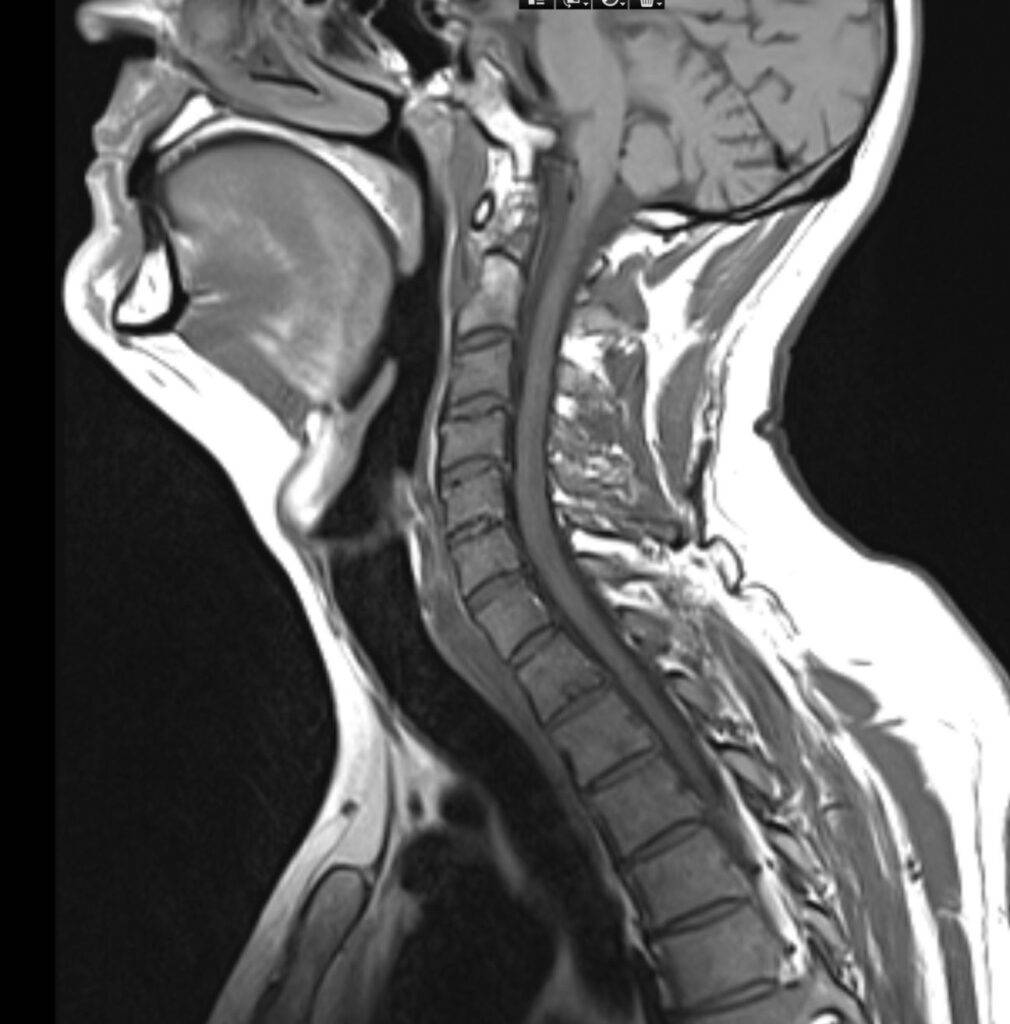

Magnetresonanztomographie (MRT):

Die MRT ist bedeutend in der modernen Orthopädie, da sie äußerst detaillierte Aufnahmen liefert:

- Weichteilstrukturen: Muskeln, Bänder, Sehnen und Knorpel werden präzise dargestellt.

- Früherkennung von Schäden: die MRT ermöglicht es, kleine Verletzungen wie Meniskusrisse oder Bänderanrisse sichtbar zu machen, die im Röntgenbild nicht beurteilbar bleiben.

- Entzündliche Prozesse: Erkrankungen wie Rheuma oder Infektionen in Gelenken können detailliert erkannt werden.

Die MRT ist nicht-invasiv und frei von Röntgenstrahlen, was sie auch für jüngere Patienten zu einer bevorzugten Methode macht.